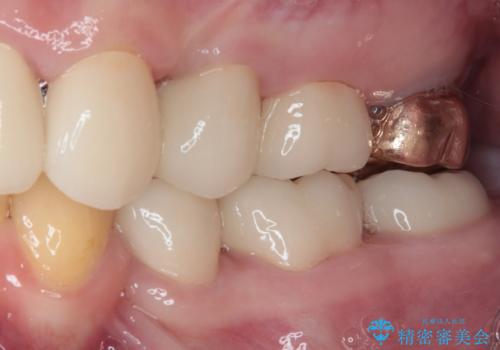

- 一時期の拒食症に伴い歯が酸で溶けてボロボロになってしまったとのことで来院された患者様です。

酸によりエナメル質の大半が溶けており、下顎前歯以外は酷いむし歯のような状態でした。

当初はほとんどの歯をむし歯治療のようにオールセラミッククラウンにて補綴治療を行う予定でしたが、仮歯に置き換えた時点で、口元の突出感や下顎前歯の叢生が気になるとのことで、上下左右の第一小臼歯4本を抜歯したワイヤー装置での抜歯矯正を行うこととしました。

矯正治療終了後に、残った歯をオールセラミッククラウンにて補綴治療を行うこととしました。